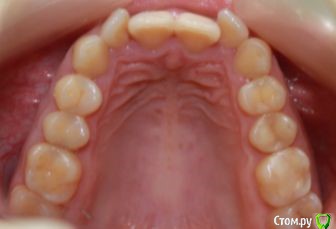

kapyulia Опубликовано 22 декабря, 2017 Поделиться Опубликовано 22 декабря, 2017 Добрый день! Могли бы Вы подсказать есть ли необходимость в удалении зубов (пятерки) с верхней челюсти? Спасибо за помощь. Ссылка на комментарий

Brigita Опубликовано 24 декабря, 2017 Поделиться Опубликовано 24 декабря, 2017 Сложно сказать без очного осмотра, по фото показаний нет. Ссылка на комментарий